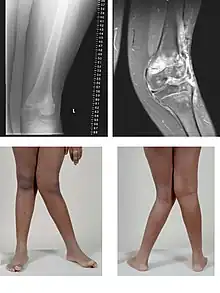

![]() | |

| A very severe case of genu valgum of the left knee following bone cancer treatment | |

Genu valgum, commonly called "knock-knee", is a condition in which the knees angle in and touch each other when the legs are straightened.[1] Individuals with severe valgus deformities are typically unable to touch their feet together while simultaneously straightening the legs. The term originates from the Latin genu, 'knee', and valgus which means "bent outwards", but is also used to describe the distal portion of the knee joint which bends outwards and thus the proximal portion seems to be bent inwards.

Mild genu valgum is diagnosed when a person standing upright with the feet touching also shows the knees touching. It can be seen in children from ages 2 to 5, and is often corrected naturally as children grow. The condition may continue or worsen with age, particularly when it is the result of a disease, such as rickets.[2] Idiopathic genu valgum is a form that is either congenital or has no known cause.